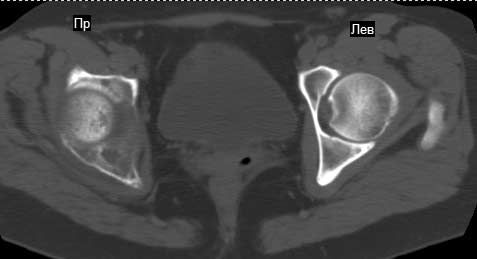

Сохранная по соматической патологии женщина ,47 лет. В 1996 г. установлен диагноз- cr левой молочной железы Т2N1Mo (2б)- проведено комплексное лечение- мастэктомия по Холстеду, ДГТ, 5 курсов ПХТ по схеме CMF. Сейчас менопауза уже 6-7 лет. В декабре 2004 года на профилактической остеосцинтиграфии с Тс99- выявлен единичный очаг повышенной фиксации препарата в зоне правой седалищной кости, рекомендована Рентгенография костей таза, выполнена- без патологии. УЗИ брюшной полости и Р-графия легких от конца апреля 2005 года - без патологии. Приблизительно 3 месяца назад появился болевой синдром в правом т/бедренном суставе с тенденцией к усилению. На рентгенограмме таза от мая 2005 года по заключению Рентгенолога очагов остеодеструкции не выявлено. Сегодня сделал ей Кт костей таза (картинки в приложении)- очаг деструкции в правой седалищной кости в зоне крыши вертлужной впадины.Что можно и нужно сделать? Жду советов, мнений, предложений по дальнейшей тактике ведения больной. С уважением, Корнев А.В.